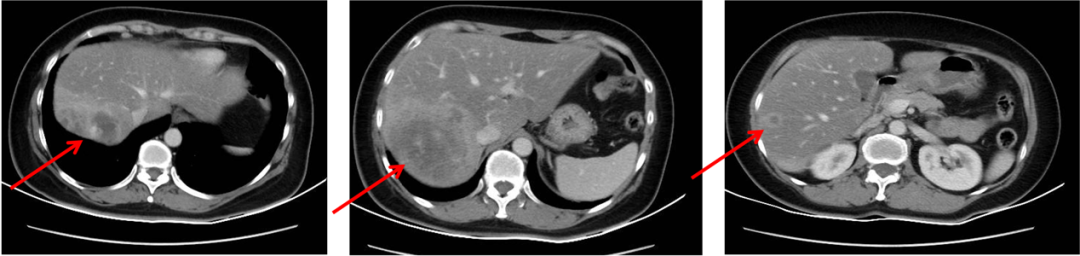

▌二线治疗:

于2015-12-18至2016-05行EC化疗6周期,具体:表柔比星90mg/m2 150mg,环磷酰胺600mg/m2 1000mg d1,Q21d。最佳评效:缩小的SD,2016-5-16改为卡培他滨维持治疗6月,具体:卡培他滨 1.5g bid d1-d14,q21d(1月后因周身不适减量至1.0g bid)。2016-11复查出现新发肝转移,评效PD。PFS为11月。

图3. 二线治疗